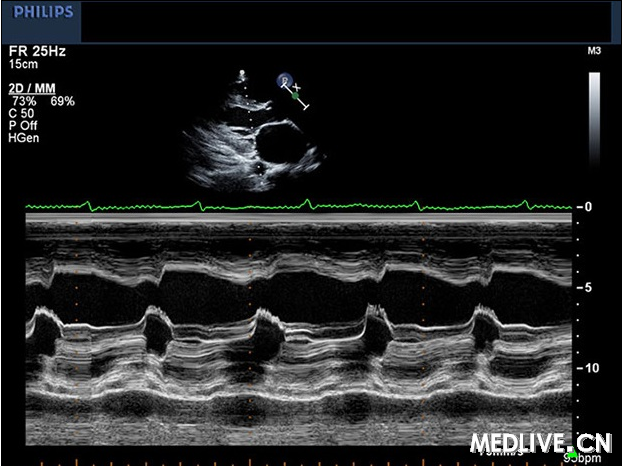

图76-1 入院后超声心动图

挑战超声心动:这位心衰患者怎么了(答案公布)

m型超声心动图